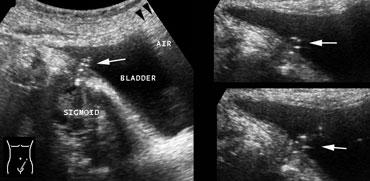

Bên trái là hình ảnh rò đại tràng-bàng quang do viêm túi thừa đại tràng sigma.

TRÁI: Từ lòng đại tràng sigma, có thể theo dõi đường khí (mũi tên) chạy suốt đến bàng quang.

PHẢI: Tại vòm bàng quang, quan sát thấy khí (đầu mũi tên). Từ lỗ mở của đường rò, có thể quan sát thấy sự di chuyển của các bóng khí (mũi tên) theo từng thời điểm.